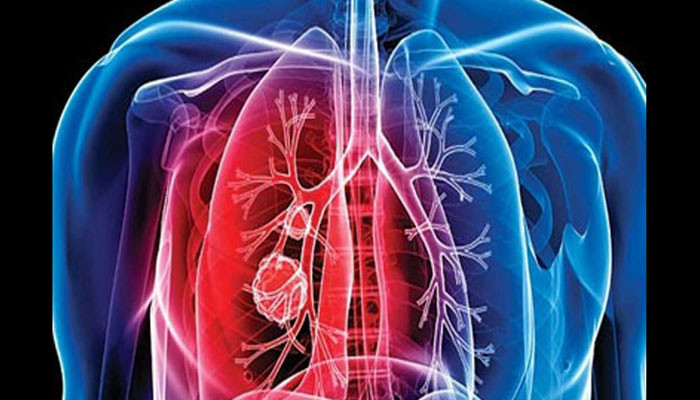

ٹی بی کے ماہر ڈاکٹر عامر کا کہنا ہے کہ پاکستان میں ٹی بی (تپِ دق) کے مریضوں کی تعداد میں اضافہ ہو رہا ہے۔

اسلام آباد میں تقریب سے خطاب کرتے ہوئے ماہر تپ دق ڈاکٹر عامر نے کہا ہے کہ روزانہ کی بنیاد پر 132 افراد صرف ٹی بی کے باعث موت کے منہ میں چلے جاتے ہیں۔

انہوں نے کہا کہ پاکستان میں ٹی بی کے عالمی صحت کے بحران نے سنگین رخ اختیار کر لی ہے، ٹی بی کے پھیلاؤ کے حوالے سے پاکستان عالمی سطح میں 5ویں نمبر پر ہے۔

ان کے مطابق ٹی بی کنٹرول پروگرام کے باوجود مریضوں کی تعداد میں اضافہ تشویشناک ہے۔

ڈاکٹر عامر نے زور دیا کہ 22 ستمبر کو ہونے والے یو این ٹی بی کنٹرول پروگرام میں وزیراعظم کو شریک ہوناچاہیے۔